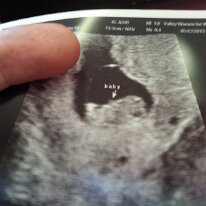

I'm Going To Be A Dad